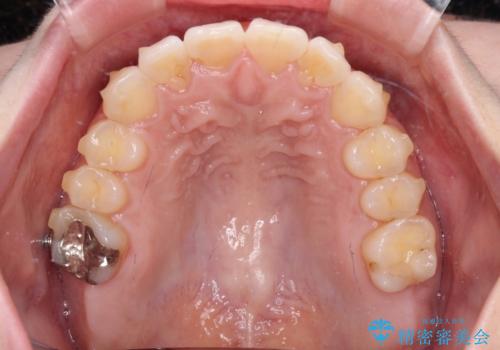

上顎前歯が捻れて前方に飛び出しており、下顎前歯もそれに沿うようにデコボコとなっていました。

IPR(歯と歯の間を削る処置)によりスペースを獲得して上下顎前歯のデコボコを改善し、飛び出している前歯が引っ込むように設定し、インビザラインにて矯正治療を行うこととしました。

左右ともに、上顎第二大臼歯が欠損しており、下顎の第二大臼歯が十分に咬み合う歯がない状態のため、放置しておくと下顎の奥歯が挺出してくる可能性があります。

安定した咬み合わせを維持するためにも、将来的に上左右にインプラント補綴が必要となります。